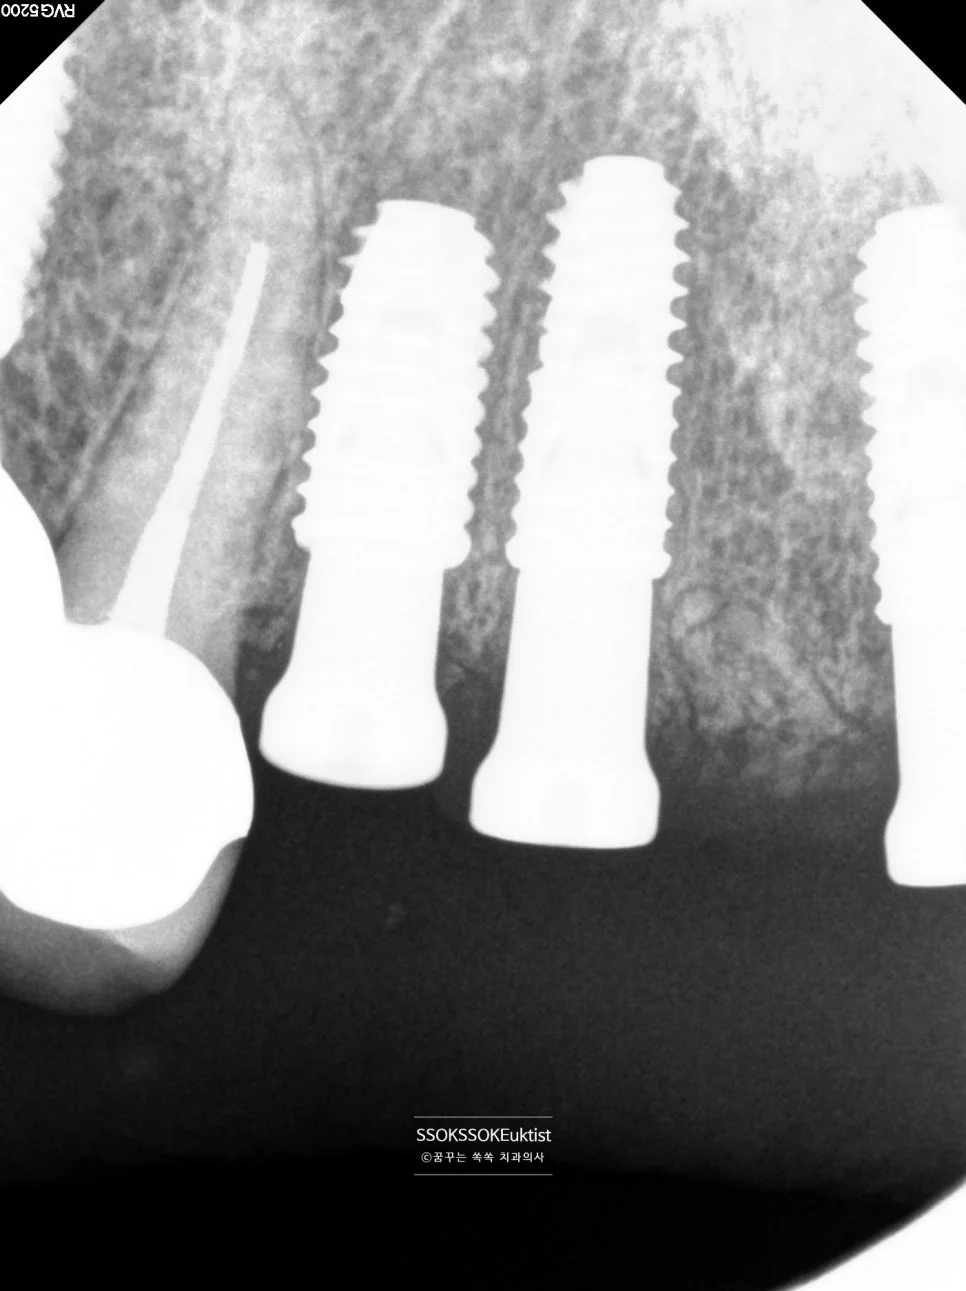

Step 5. 치근단 X-ray 확인

치근단 X-ray – 주변 뼈보다 2~3mm 깊이로 식립 확인

주변 뼈보다 2~3mm 깊이로 식립된 모습이니 임플란트 치료가 잘 되었다고 볼 수 있겠죠.